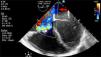

Por severidad del cuadro clínico, inestabilidad hemodinámica y respuesta pobre al manejo se consideró repetir el ecocardiograma, esta vez de forma transesofágica en equipo CX50 portatil, transductor S5-1, por daños valvulares previamente documentados. Éste mostró ventrículo izquierdo de tamaño normal sin disfunción sistólica con solución de continuidad de 9mm en el seno no coronariano, en directa relación con la aurícula derecha por encima de la válvula tricúspide (figs. 1 y 2), gradiente pico de 70mm Hg, válvula mitral e insuficiencia leve, válvula aórtica bivalva e insuficiencia leve, válvula tricúspide engrosada e insuficiencia leve que no permitió calcular la presión sistólica pulmonar, aurícula derecha severamente dilatada (30cm2), dilatación moderada del ventrículo derecho, diámetro basal (45mm) y medio de (39mm), sin disfunción sistólica TAPSE 20mm, pericardio sin colecciones y foramen ovale de 4mm con cortocircuito de izquierda a derecha (fig. 1).